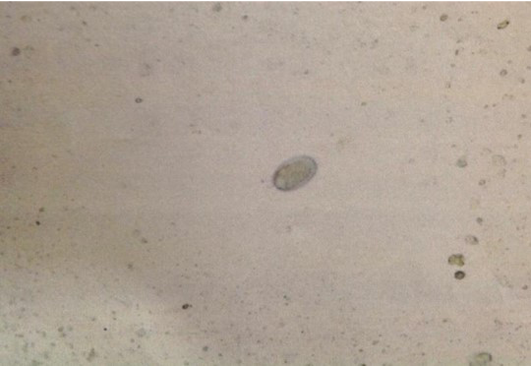

Figure 1

Ancylostoma spp. egg